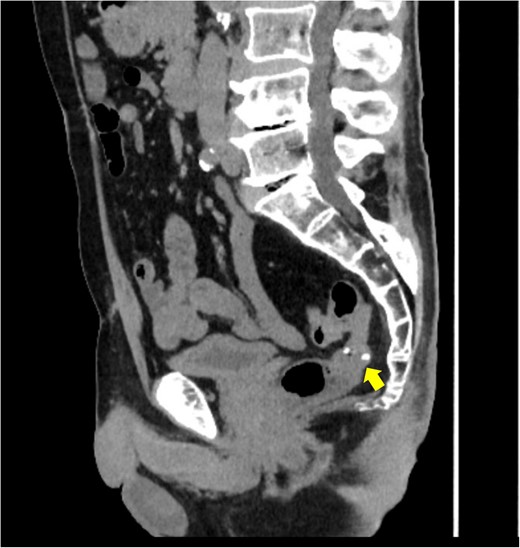

A 72-year-old man diagnosed with NSCLC was referred for possible surgical treatment of a solitary nodule detected in the mesorectum. His medical history included hypertension and endoscopic resection of colonic polyps, with no prior thromboembolism. He had received combined medical treatment for NSCLC (cT4N0M0, stage IIIA) (Fig. 1), including four courses of cisplatin and docetaxel chemotherapy with a 60 Gy/30 fractions radiation dose, followed by 1 year of consolidation therapy with durvalumab (640 mg/body). The patient tolerated the treatment well, achieving a complete response 13 months before presentation (Fig. 2). However, the mesorectal nodule was incidentally discovered during surveillance CT after NSCLC treatment completion. It was round, 15 mm in diameter, showed contrast enhancement, and was near the mesorectal vessels (Fig. 3a and b). An FDG PET/CT scan revealed a solitary mesorectal nodule with an SUVmax of 10.3 (Fig. 4). Consequently, the radiologist suggested differential diagnoses of malignant lymphoma and metastatic lymph nodes from the urinary or lower gastrointestinal tract, as NSCLC typically does not metastasize to mesorectal lymph nodes. No other abnormal FDG uptake was observed. Laboratory tests showed normal levels for tumor markers, including carcinoembryonic antigen, sialyl Lewis X (SLX), squamous cell carcinoma antigen, neuron-specific enolase, cytokeratin fragment (CYFRA), progastrin-releasing peptide, and blood coagulability was within the normal range. Total colonoscopy revealed no neoplastic lesions, and urinary cytology showed nonmalignant urothelial cells. Noninvasive diagnostic approaches, including endoscopic or CT-guided biopsy, were extensively discussed but deemed difficult because of anatomical restrictions, risk of dissemination, and procedure-related complications (such as bleeding or perforation). Because of the potential malignancy and need for en-bloc resection, we opted for surgical resection using a standardized laparoscopically assisted mesorectal excision technique. During rectal dissection, the nodule was not visible through the posterior and lateral sides because it was completely embedded in the mesorectum. Therefore, a Pfannenstiel incision was made in the lower abdomen to exteriorize the rectum after the division of the proximal colon. The nodule was confirmed by direct palpation, marked with a stitch, and subsequently removed after intracorporeal transection of the distal rectum. We inspected the resected specimen and confirmed that the nodule was incorporated (Fig. 5a and b). A colorectal anastomosis was then performed using a double-stapling technique with a circular stapler. The postoperative course was uneventful, except for a slight elevation of the d-dimer level (up to 3.26 μg/ml) on postoperative Day 7, which normalized spontaneously without intensive anticoagulation therapy. The patient was discharged on postoperative Day 10. Pathological examination revealed that the 7-mm white nodule was an intravenous organized thrombus in the mesorectum surrounded by granulation tissue, with no malignancy observed (Fig. 6a and b). Postoperatively, the patient did not require additional chemotherapy or anticoagulation therapy. During the 16-month follow-up, no radiological evidence of NSCLC recurrence and thromboembolism was detected (Fig. 7).

Preoperative pelvic computed tomography (CT) image. The circle indicates the nodule located in the mesorectum. (a) Horizontal view. (b) Sagittal view.